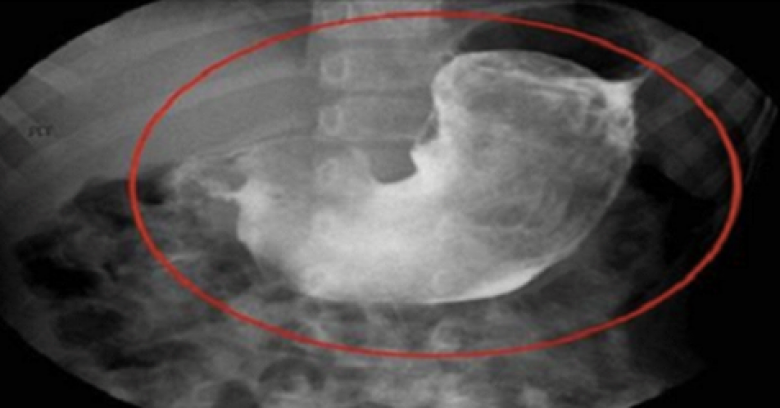

Женщина, посетившая гинеколога из-за острых болей в желудке, сделала страшное открытие

Мишель Бэрроу, которая изначально поместила свою историю на страницах женского журнала «XOJane», рассказала, что решила обратиться к гинекологу по той причине, что ощущала тупую боль в области живота.

Подозревая, что у Бэрроу, скорее всего, рак яичников, гинеколог начала обследовать ее влагалище. И именно того специалист обнаружила какие-то странные волоски внутри организма пациентки.

“Она начала обследование и сразу же стала бормотать что-то себе под нос: что это? Я никогда не видел ничего подобного. Что же это такое?’’ – описывала ситуацию Мишель!

cat

Женщина-доктор изначально подумала, что это волоски остались после использования противозачаточного средства, которое вставляется в матку. Удалив эти волоски, доктор показала комок Бэрроу – это был настоящий ‘’меховой шар’’!

«ЧЕРТ ПОБЕРИ!!! ВЫ МОЖЕТЕ В ЭТО ПОВЕРИТЬ? ВНУТРИ МОЕГО ВЛАГАЛИЩА БЫЛО ОБНАРУЖЕНО ПОЧТИ 2 ДЮЙМА КОШАЧЬЕЙ ШЕРСТИ, СВЕРНУТОЙ В КЛУБОК. ВОТ ОНА – ПРИЧИНА МОЕГО ДИСКОМФОРТА. БОЖЕЕЕЕЕЕЕЕЕЕЕЕЕЕЕЕЕЕЕЕЕЕЕЕЕЕЕЕЕЕЕЕЕЕЕЕЕЕЕЕЕЕЕ!»

Вот, как отреагировала Бэрроу после похода к гинекологу.

Дело в том, что у Мишель – две кошки, Пончик и Сверчок. И она позволяет им спать с собой в постели. И как же шерсть попала внутрь? Оказалось, эти волосики прилеплялись к половому члену ее жениха, и каждый раз, во время полового акта, несколько волосиков попадали ей во влагалище!